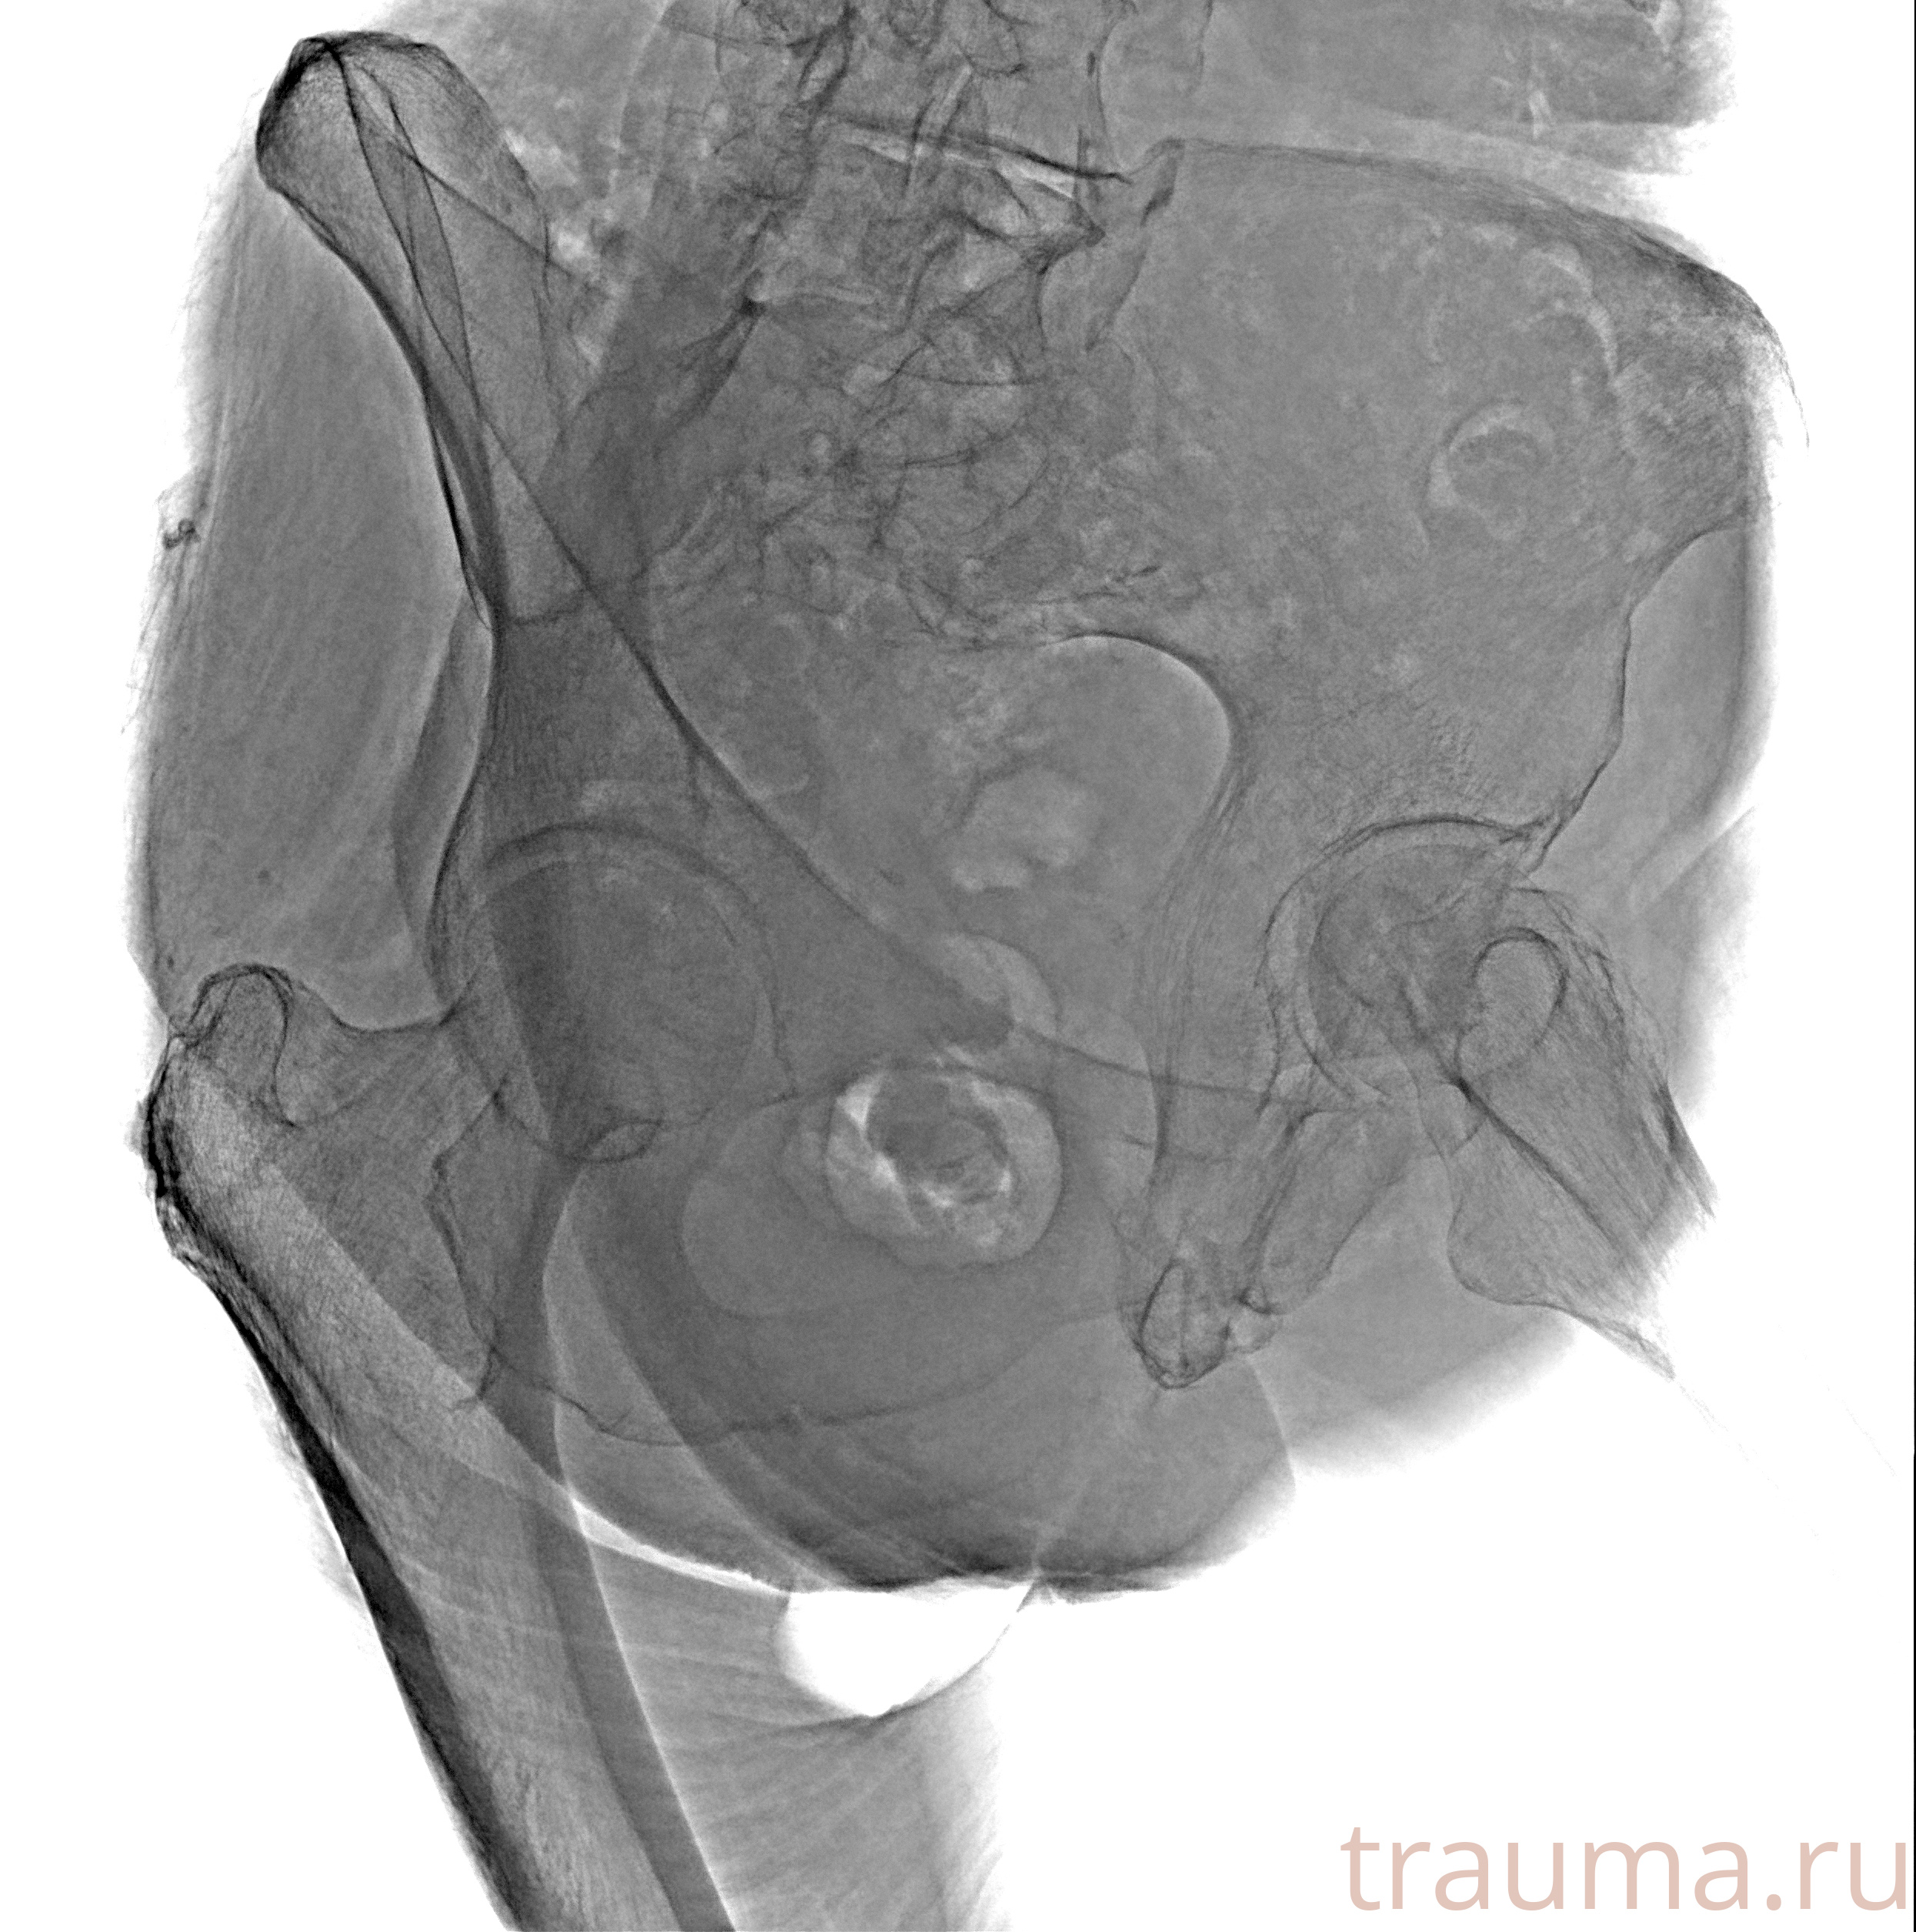

Рентген на дому: по вашему адресу приезжает врач-рентгенолог, травматолог-ортопед с мобильным рентгеновским аппаратом, проводит диагностику травмы или заболевания, делает необходимые рентгенограммы, дает рекомендации по дальнейшему лечению. Получить качественные снимки в домашних условиях возможно благодаря уникальной методике, разработанной МосРентген Центром для института  Склифосовского